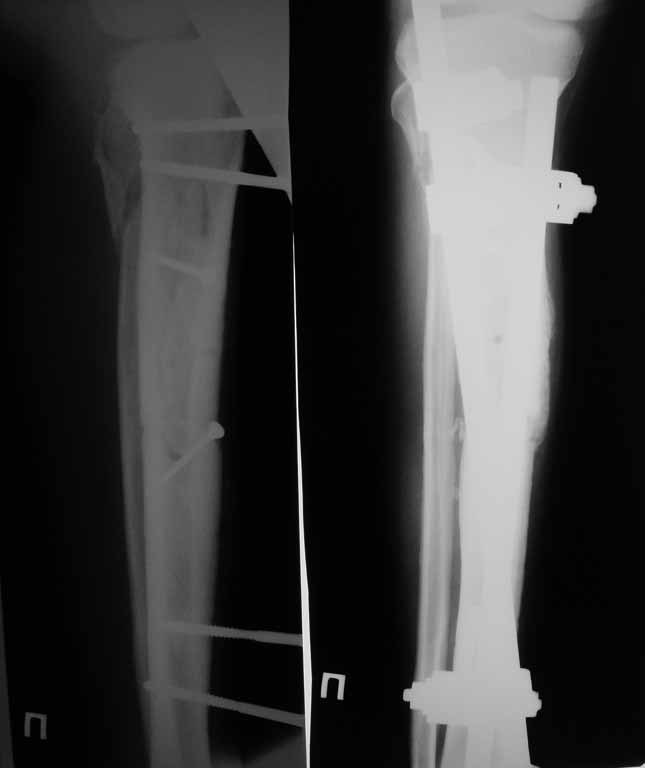

Привожу пример: Пациент с открытой тяжелой ЧМТ.

Диагноз при поступлении: Открытый оскольчатый перелом свода и основания черепа,субдуральная гематома, ушиб головного мозга тяжелой степени. Открытый оскольчатый перелом костей правой голени. Шок 3 Кома 3

При поступлении оперирован : трепанация, ПХО, остеосинтез голени.

Консолидация в аппарате внешней фиксации к 2 месяцам. Аппарат снят через 2,5 месяца.

Фото в приложении.